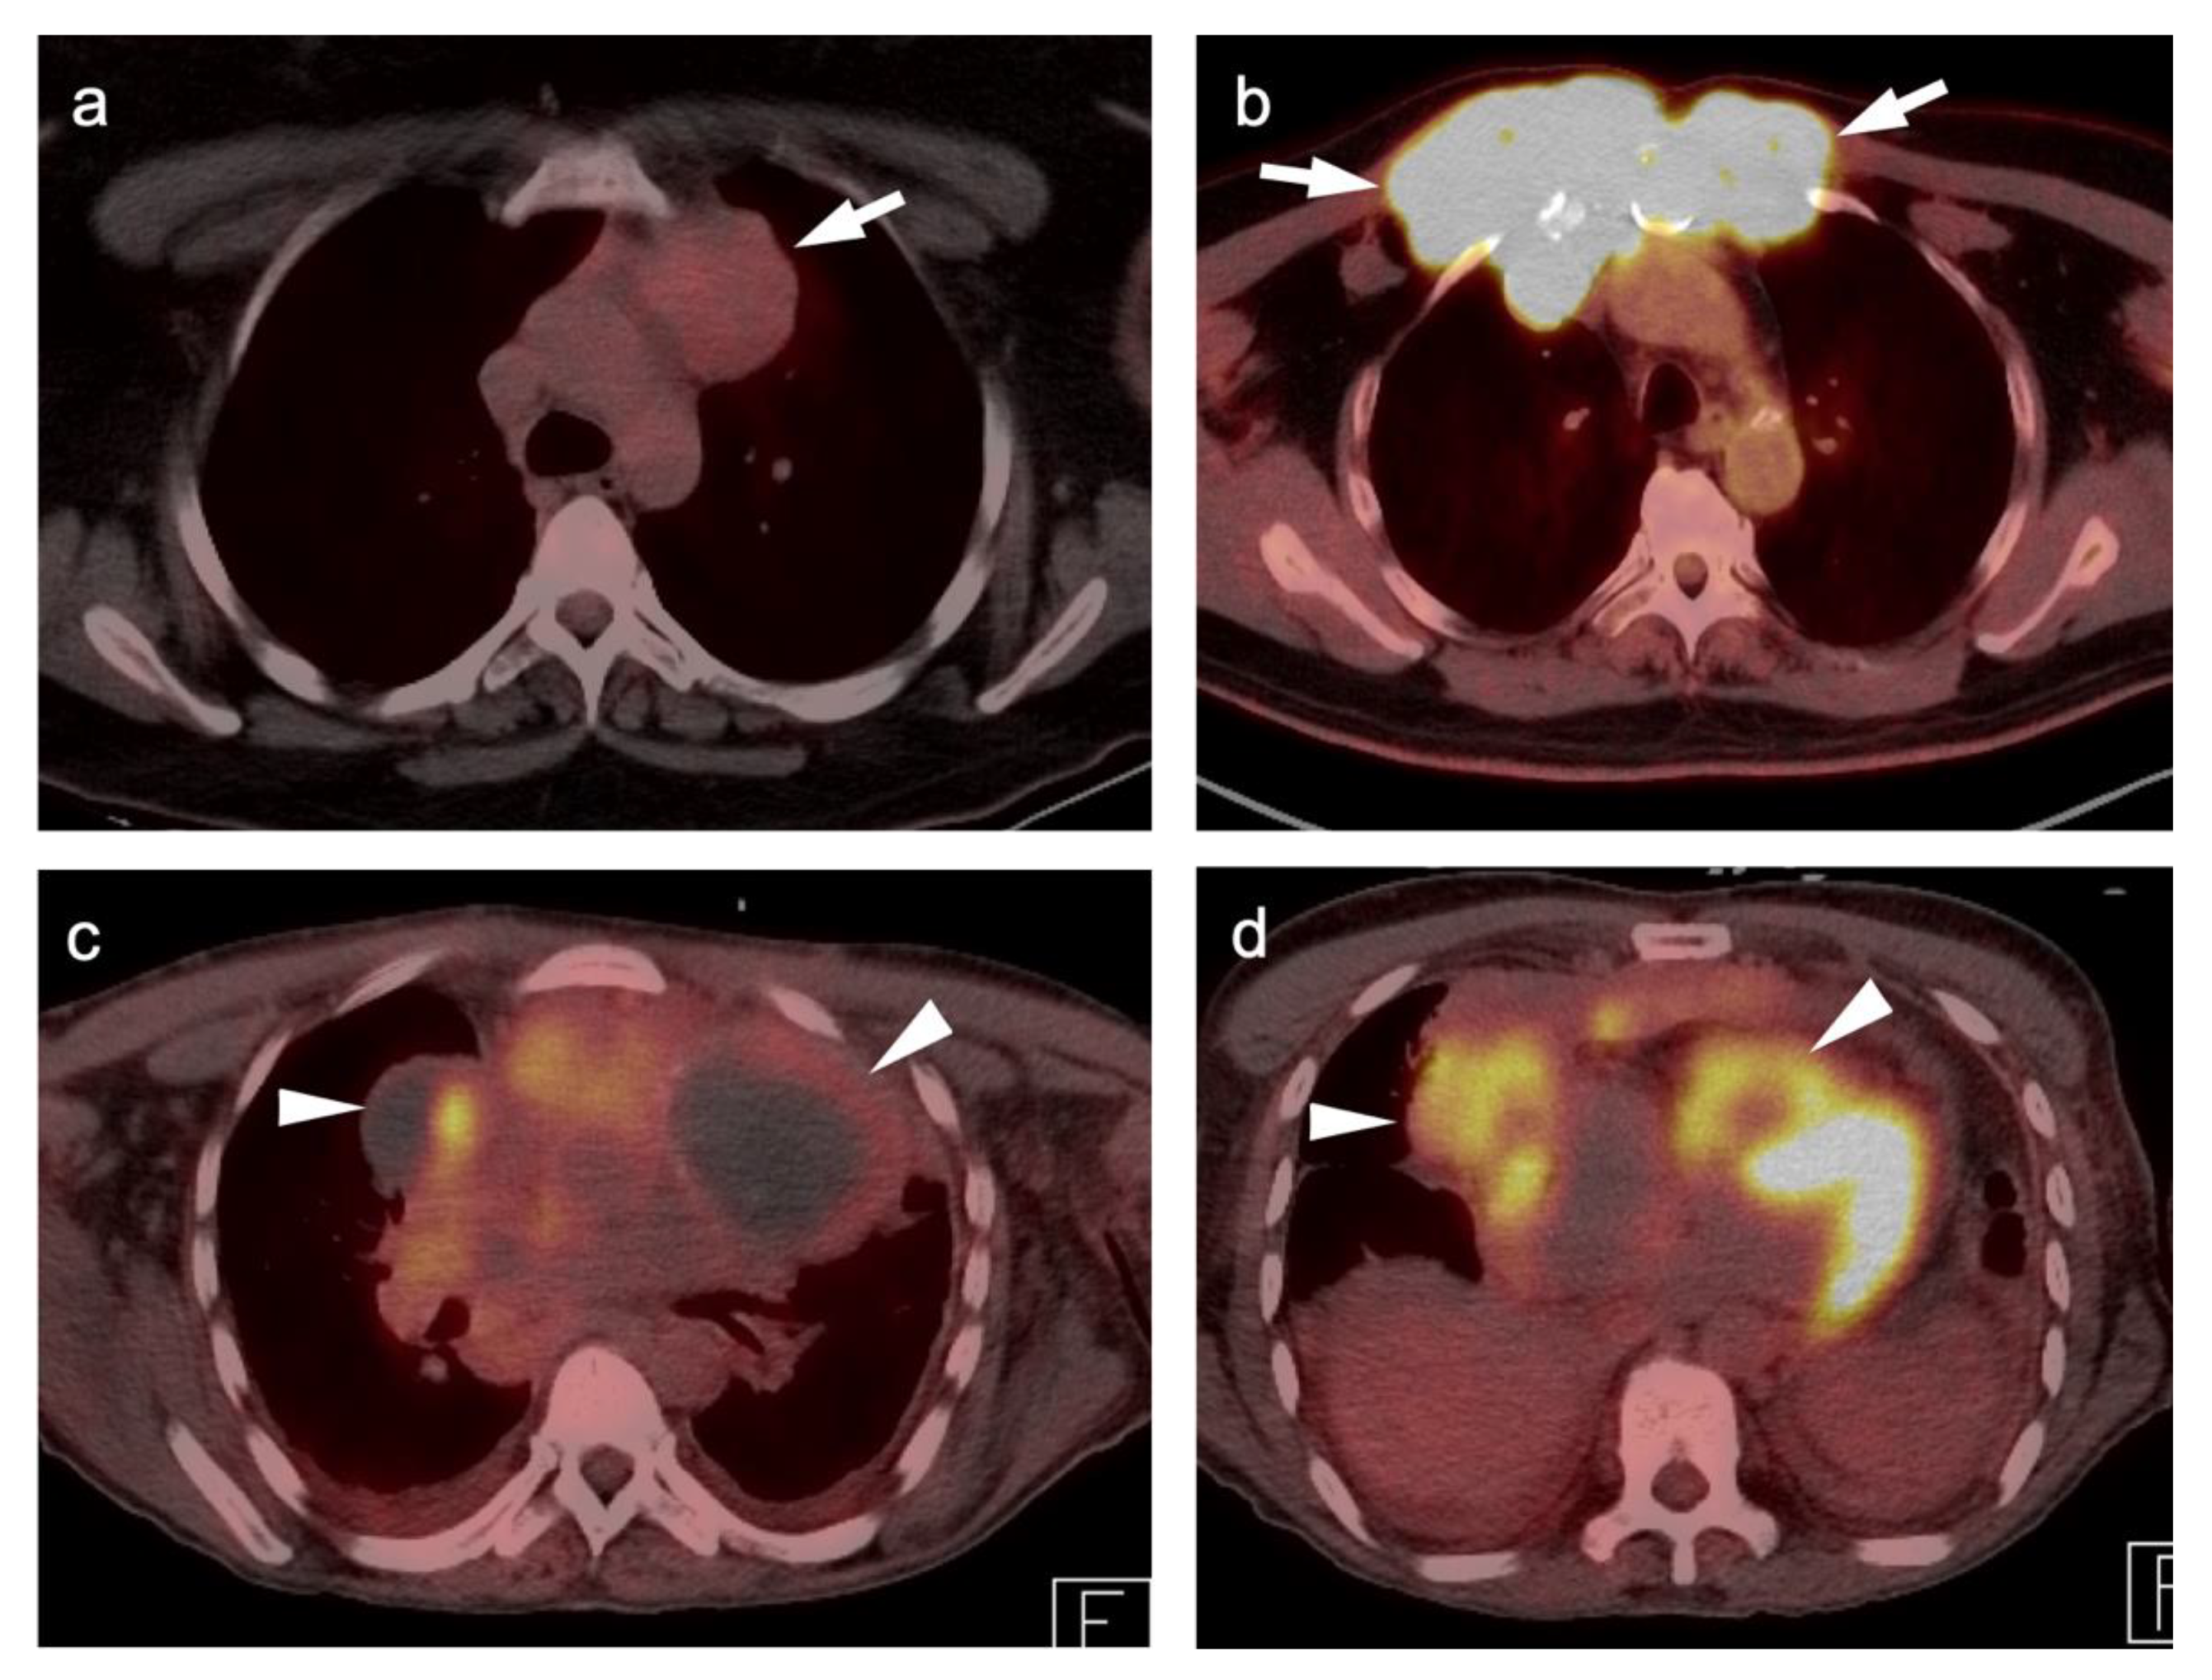

In Refs. [15,28], T staging describes the location, size, and extent of the primary tumor, as well as the presence of absence of satellite nodules. Given its excellent anatomical resolution, CT remains an important modality for T stage assessment although its ability to evaluate soft tissue invasion and its ability to distinguish primary lesions from post-obstructive atelectasis is limited. FDG PET-CT significantly improves T staging, due to its precise CT correlation with the degree of FDG uptake (Figure 8). Multiple studies have shown that integrated PET-CT provides crucial information on mediastinal infiltration and chest wall invasion, and aids in differentiating between tumor and post-obstructive atelectasis [2,29].

N staging identifies nodal involvement in lung cancer is of paramount importance, especially in patients with mediastinal disease without distant extra-thoracic disease. In these patients, the N stage will have therapeutic and prognostic implications [29]. In describing areas of nodal involvement, it is important to identify the specific nodal location involved, as outlined by the IASCL, as this will affect the N classification [26]. Patients staged as N0 or N1, without lymph node involvement, are generally treated with local intervention, and patients with N2 disease with ipsilateral mediastinal lymph node metastases might benefit from a combined approach with local and systemic therapies. N3 diseases with contralateral mediastinal lymph node metastases are considered incurable and will eventually require palliative care [2]. FDG PET-CT has advantages over CT alone, even when the lymph nodes are smaller than 10 mm in diameter [2,30]. FDG PET-CT is of crucial importance in evaluating nodal sites that are inaccessible to mediastinoscopy, such as the aortopulmonary window, anterior mediastinum, and posterior subcarinal nodes. Even though FDG PET-CT is an excellent noninvasive imaging modality in the detection of nodal metastatic involvement, mediastinoscopy remains the gold-standard and needs to be performed wherever there is ambiguity or uncertainty with regard to the status of any one lymph node in patients with NSCLC (Figure 9).

Nearly half of all patients with NSCLC have distant metastatic disease at initial diagnosis and identification of distant metastases is of major importance in the management and prognosis. Additionally, among patients who have been treated with radical and supposedly curative therapy, approximately 20% are likely to develop recurrent disease due to undetected foci of metastasis at initial M staging. Distant metastases are most commonly seen involving the brain, skeleton, liver, and adrenal glands in descending order of frequency (Figure 10) [31]. Traditional evaluation for distant metastatic disease includes CT scans of chest, abdomen, and pelvis, brain imaging with CT or MRI and bone scintigraphy [2]. However, FDG PET-CT has been shown to be great utility in M staging of the patients with NSCLC, specifically if the patients present with clinical manifestations of metastatic disease. Additionally, FDG PET-CT has been shown to provide more pertinent information during the preoperative assessment than is CT alone, except in the assessment of brain metastases, in a situation where the two modalities yield similar results [32]. For staging mediastinal lymph nodes, diffusion-weighted imaging MRI (DWI) and FDG PET-CT showed similar performance in staging of mediastinal lymph nodes, supporting the idea that DWI may offer an alternative to FDG PET-CT in some cases [33].